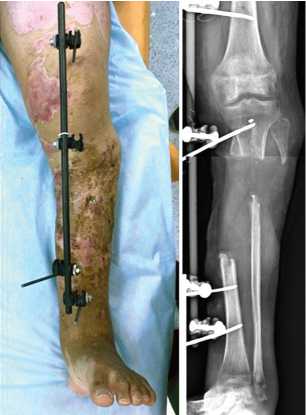

Пациент 44 лет (группа 2) получил ранение при участии в боевых действиях. Диагноз: Сочетанное взрывное поражение таза, обеих нижних конечностей. Множественные осколочные раны промежности, нижних конечностей. Обширная рваная рана правой голени, оскольчатый перелом обеих костей в верхней и средней трети с первичным дефектом костной и мягких тканей (рис. 7). Обширная рваная рана левой стопы с переломом 1 и 2 плюсневых костей. Острая массивная кровопотеря. Травматический шок 2 степени. Острое повреждение почек.

После стабилизации состояния и восстановления функции почек через 34 дня после ранения выполнили повторную хирургическую обработку раны, некрэктомию большеберцовой и малоберцовой костей, ОУ правой голени, ВЧКДО по Илизарову. Дефект большеберцовой кости составил 11 см (рис. 8).

Через 126 дней после ранения (на 92-е сутки после ОУ) выявили признаки сращения отломков и выполнили остеотомию в нижней трети большеберцовой кости (рис. 9 и 10, а).

Рис. 7. Фото и рентгенограмма правой голени при поступлении

Рис. 8. Рентгенограмма правой голени после острого укорочения

Рис. 9. Фото правой голени перед остеотомией